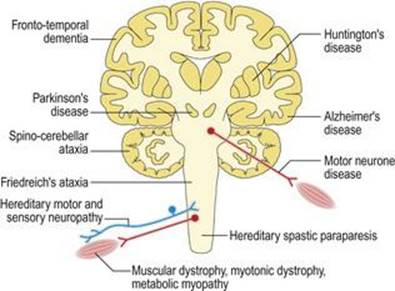

اختلالات سیستم عصبی عضلانی چهار نوع عمده هستند (شکل ۱.۳۰) در رابطه با علت یا علت.

شکل ۱.۳۰ چهار دسته عمده اختلالات سیستم عصبی عضلانی.

شکل ۱.۳۰ چهار دسته عمده اختلالات سیستم عصبی عضلانی.

اختلالات درونی

اختلالات درونی (شکل ۱.۳۴) اختلالات اولیه خود سیستم عصبی هستند. اختلالات عصبی اولیه درونی ناشایع و اغلب مزمن و غیرقابل برگشت هستند، به طوری که میتوان یک سری تحقیقات آرامتر را انتخاب کرد. بسیاری از اختلالات عصبی تحت تأثیرات ژنتیکی قرار دارند (هرادو-دژنراسیون). خطاهای ذاتی متابولیسم منجر به ناهنجاری ذهنی و ناتوانی در کودکان میشود و معمولاً ناشی از کمبود آنزیمهای خاص است. اختلالات حمله ای شامل از دست دادن اپیزودیک هوشیاری (صرع)، خواب زیاد (نارکولپسی) و سردرد (میگرن) است. انحطاط سیستم (شکل ۱.۳۵) در جوانی و پیری رخ میدهد و منجر به مرگ زودرس (آتروفی) برخی از اجزای عصبی عضلانی، با صرفه جویی در سایر اجزا میشود. هنگامیکه انحطاط سیستم در جوانی رخ میدهد، اغلب یک علت ارثی یا ژنتیکی آشکار دارد: به عنوان مثال، دیستروفیهای عضلانی، نوروپاتیهای حسی حرکتی ارثی، پاراپارزی اسپاستیک ارثی، آتاکسیهای مخچه و بیماریهانتینگتون. هنگامیکه آنها در اواخر زندگی رخ میدهند اغلب پراکنده هستند: به عنوان مثال بیماری نورون حرکتی، بیماری پارکینسون و بیماری آلزایمر.انحطاط سیستم به طور قابل ملاحظه ای انتخابی هستند. به عنوان مثال، در بیماری نورون حرکتی فلج عضله وجود دارد اما هیچ اختلالی در حس وجود ندارد، در حالی که در بیماری آلزایمر، فراموشی شدید اما فلج وجود ندارد.

شکل ۱.۳۴ اختلالات درونی سیستم عصبی عضلانی. رنگها به شکلهای ۱.۳۵ – ۱.۳۹ مراجعه میکنند.

شکل ۱.۳۴ اختلالات درونی سیستم عصبی عضلانی. رنگها به شکلهای ۱.۳۵ – ۱.۳۹ مراجعه میکنند.

شکل ۱.۳۵ اختلالات دژنراتیو سیستم عصبی عضلانی.

شکل ۱.۳۵ اختلالات دژنراتیو سیستم عصبی عضلانی.